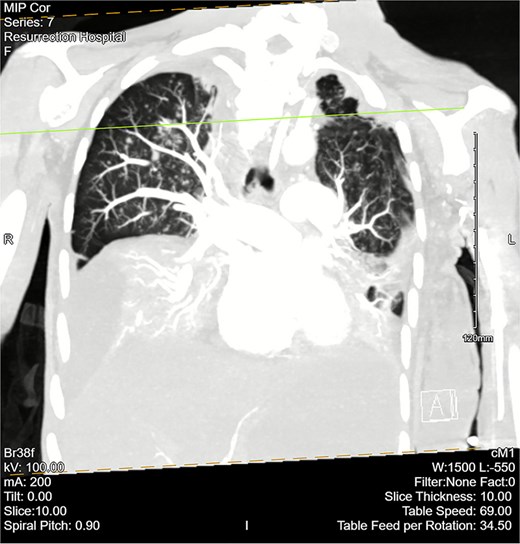

Computed tomography (CT) angiogram of the chest demonstrated numerous small nodular and patchy opacities throughout the upper lobes ranging from punctate to 1.2 cm in diameter (Figs 1 and 2). Additionally, bilateral pleural effusions with extensive atelectasis were also observed.

CT chest angiogram with a coronal cross section. Bilateral pleural effusions with atelectasis are observed. Ground-glass opacities with scattered nodules are present in the upper lobes. Lung volumes are reduced. There are no signs of embolism in pulmonary arterial segments.